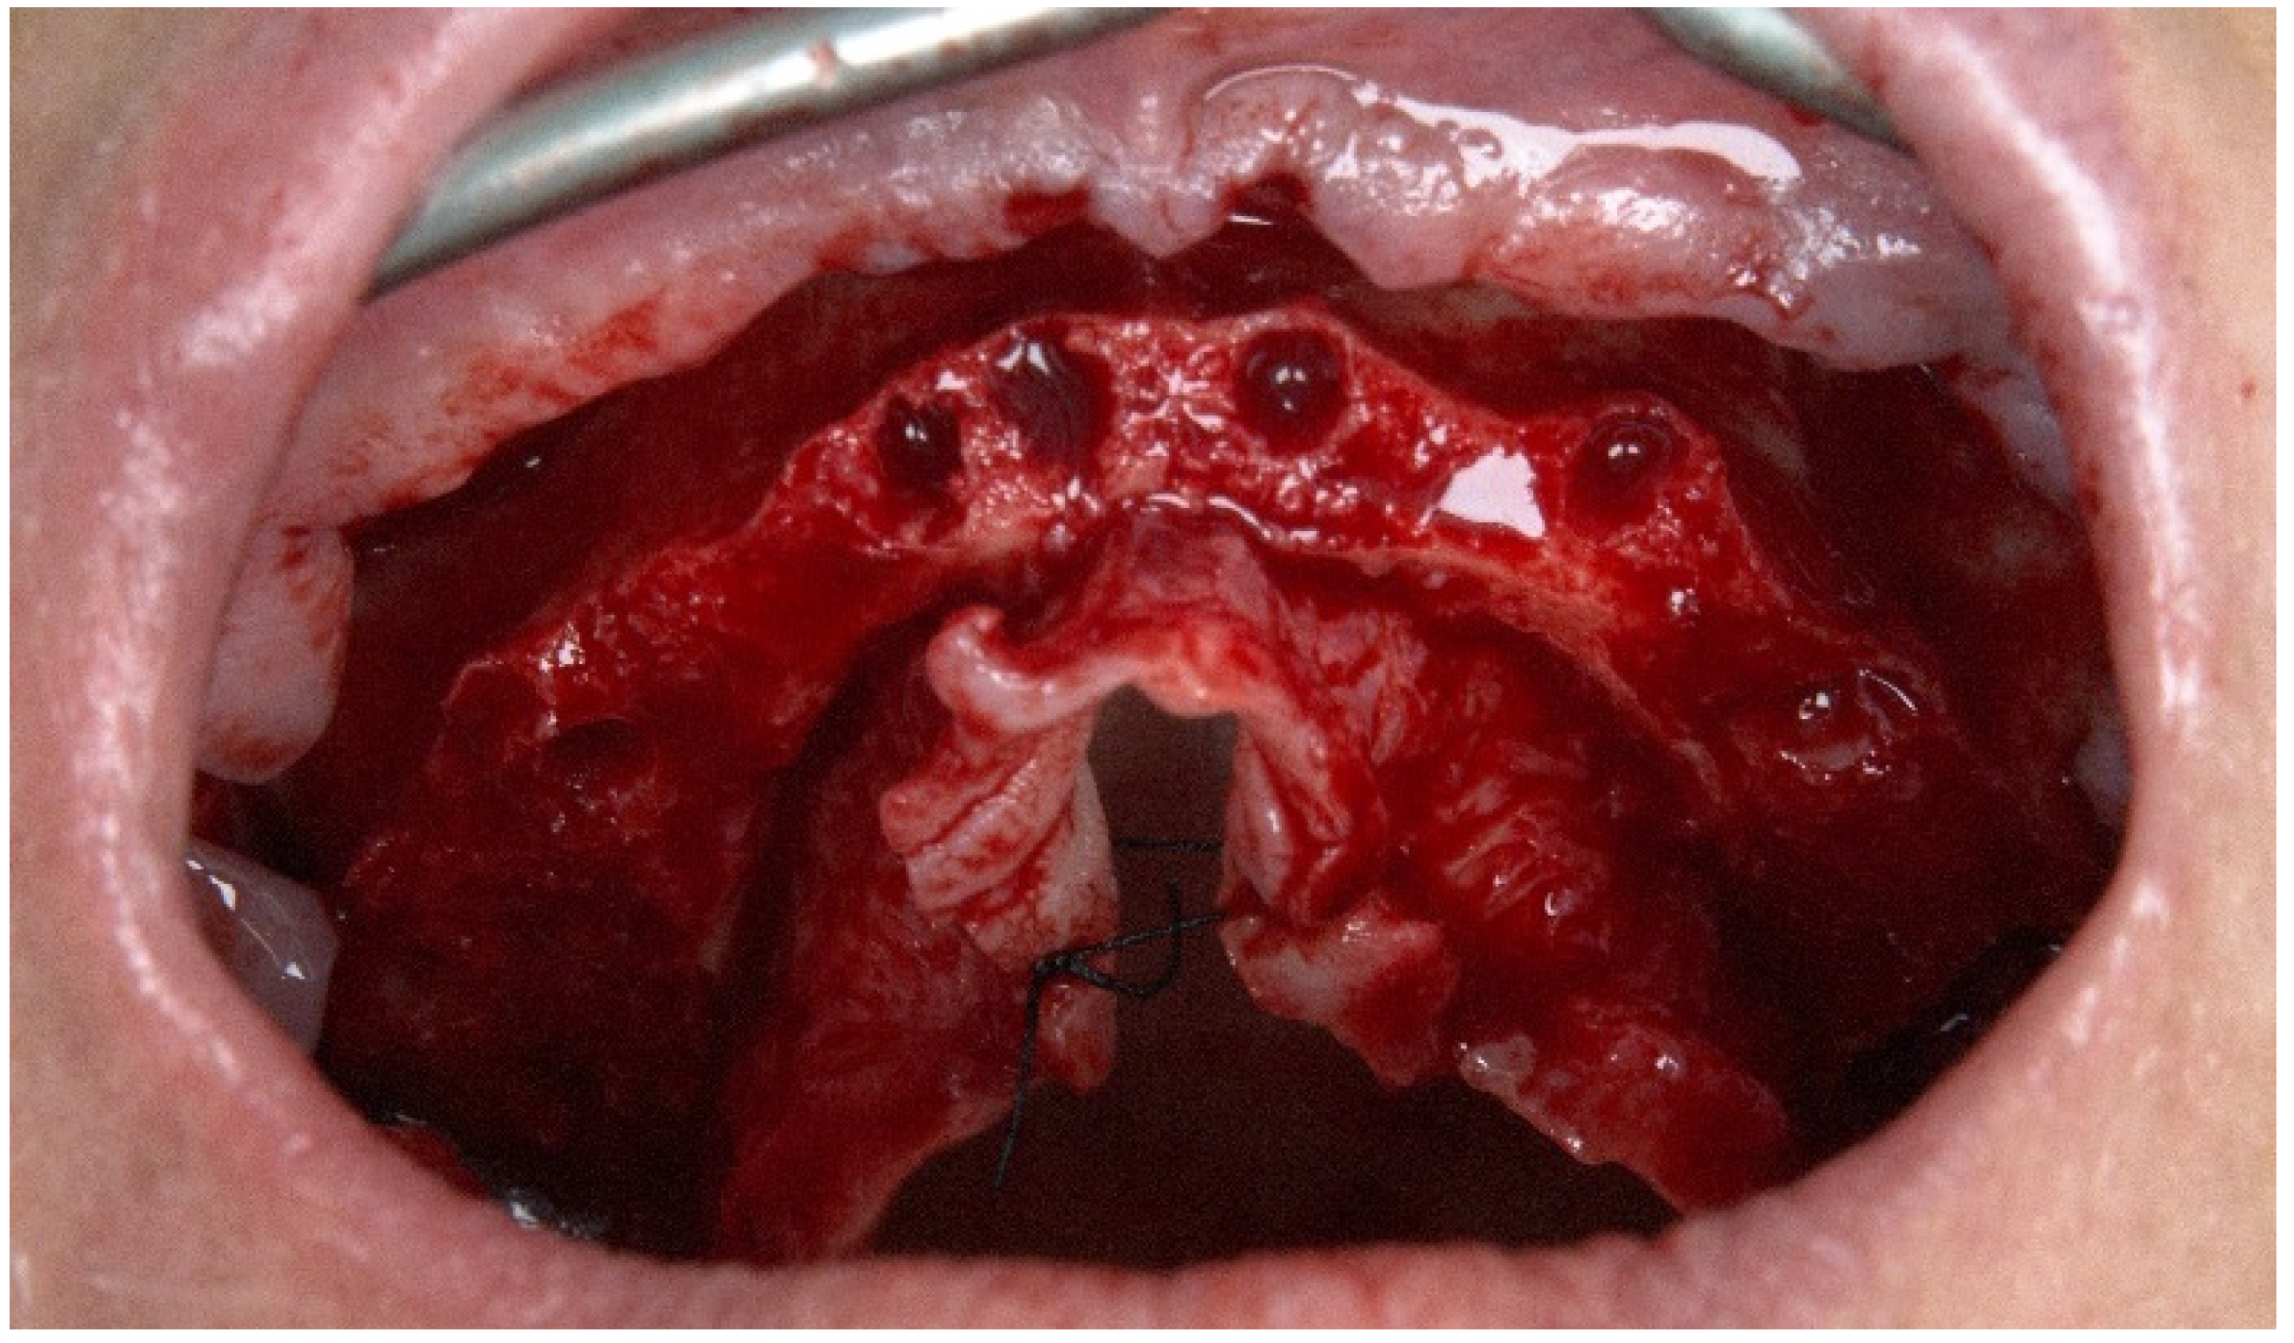

2.1. Patient 1